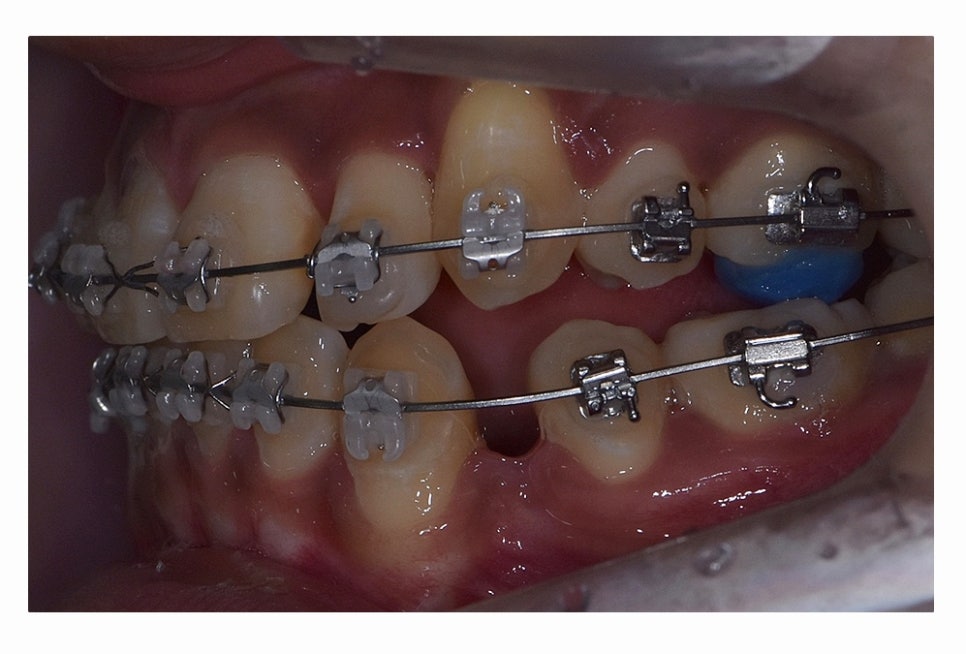

오늘 보시는 환자분의 사례처럼 덧니가 치아끼리 겹쳐 있는 경우에

치아의 이동 공간 확보를 위해서 덧니 발치 필요한 사례였으며

교합과 치아교정 후 얼굴 변화를 고려할 때도 치아교정 과정에서

발치가 필요한 사례였다고 볼 수 있어요.

치아교정 과정에서 덧니 발치 필요한 경우에는 덧니 자체를

발치한다고 생각하시는 분들도 계신데

꼭 그렇지는 않으며 앞서 설명드린 것처럼

치아의 이동 공간 확보와 교합을 고려하여 발치가 이뤄지고 있어요

일반적으로는 송곳니 옆의 작은 어금니를 발치하는

경우가 대부분이며 손상이 심한 치아가 있는 경우에는

손상도가 심한 치아를 발치하는 경우도 있어요